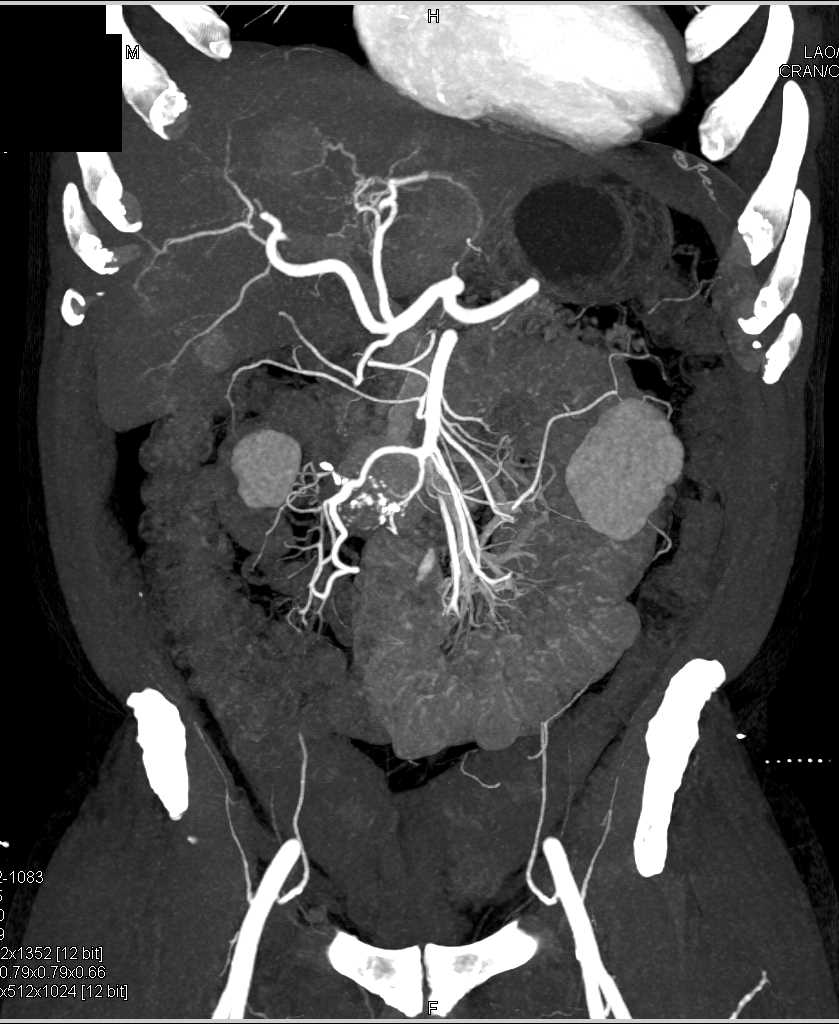

Carcinoid Tumor with Desmoplastic Reaction